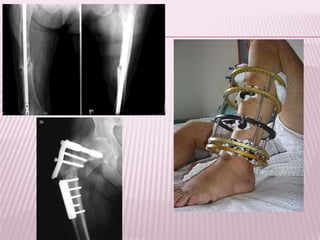

TRATAMIENTO

ortopédico

quirúrgico

Reducción lenta y continua (tracción

esquelética)

Se elevan los pies del paciente

poniendo un realce, para que el cuerpo

actué de contrapeso. Se coloca férula

de Braun. (Control radiográfico)

En caso de tener una

fractura distal o

supracondílea (Férula de

Putti)

Puede completarse con yeso

pelvipédico, 3-4 meses

continuando con traccion hasta la

consolidación.

Enclavado intramedular de

Küntscher: Clavo de corte trebolar por

dentro del conducto medular.

Placas de compresión: Reducción

anatómica e inmovilización rígida

(retardo de la consolidación)

Fijadores externos: Colocación

a cielo cerrado de tornillos

perpendiculares al eje del

hueso, unidos por un dispositivo

externo,